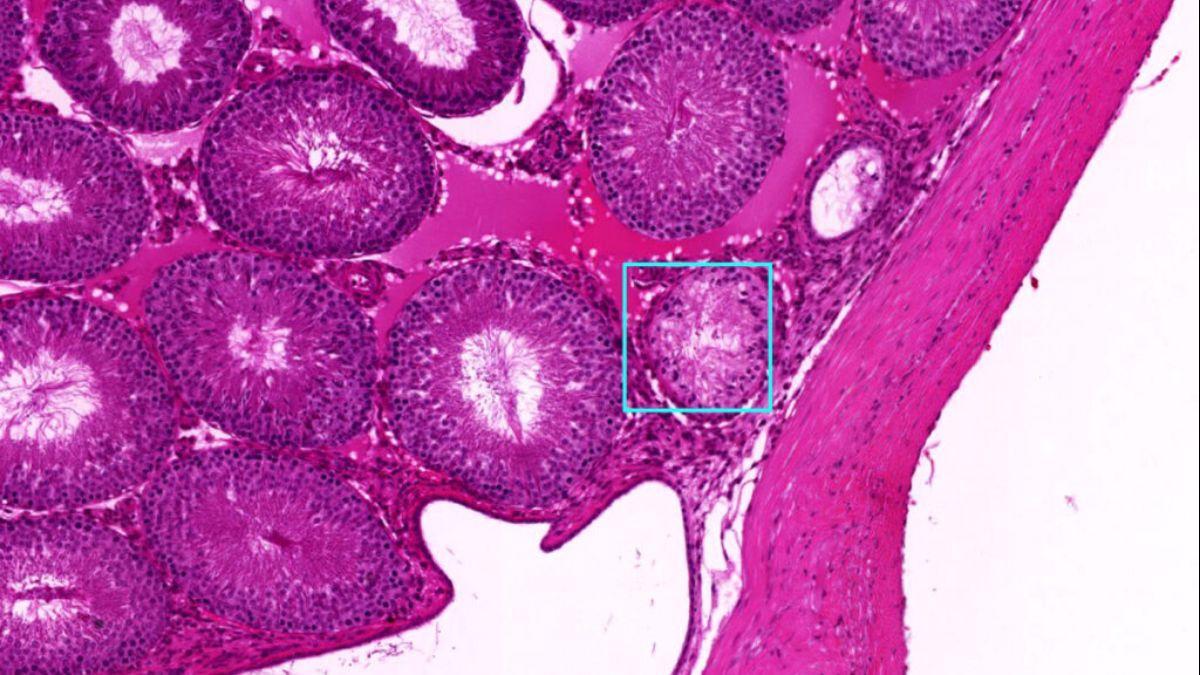

El modelo de Inteligencia Artificial desarrollado por los investigadores pudo identificar patologías mucho más rápido que los humanos, a veces detectando signos que los médicos habían pasado por alto. / Créditos: Eric Nilsson, Skinner Laboratory, WSU.

En el nuevo estudio, los investigadores estadounidenses desarrollaron y presentaron un enfoque de aprendizaje profundo que puede ser entrenado para localizar y clasificar con precisión diferentes tipos de patologías en una amplia variedad de tejidos y estructuras, como testículos, ovario, próstata y riñón. El procedimiento se optimizó y validó mediante el análisis de distintos ejemplos.